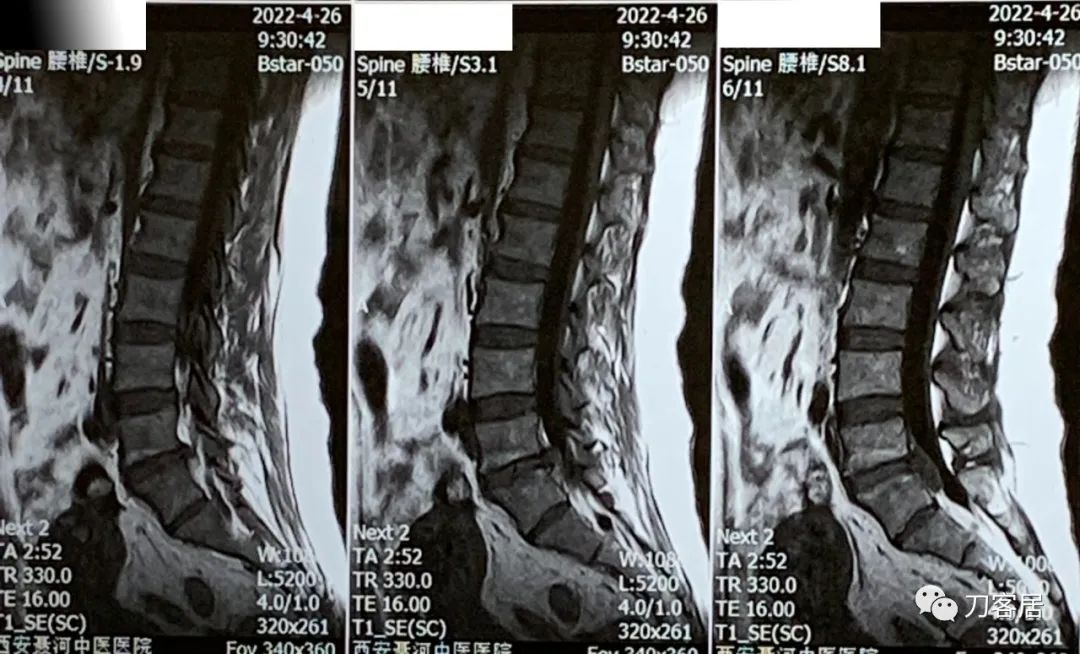

现病史:行走动作慢,不能快走,可行走1km, 咳嗽及打喷嚏时无加重,近1周理疗后缓解,1周前间歇性跛行30米。自带腰椎MRI提示腰5骶1椎间盘突出。4月26日腰椎MRI提示腰5骶1椎间盘突出巨大,已脱落进入椎管,5月28日复查腰椎磁共振提示腰5骶1椎间盘突出,较4月26日有缩小,或有吸收,患者大小便无异常,患者不想手术,可考虑先试行保守治疗。如症状无缓解,或有加重,再手术。禁忌推拿按摩,患者较胖,建议功能训练,减肥。

图4. 20220426西安长安聂河中医院腰椎磁共振03

图5. 20220426西安长安聂河中医院腰椎磁共振04